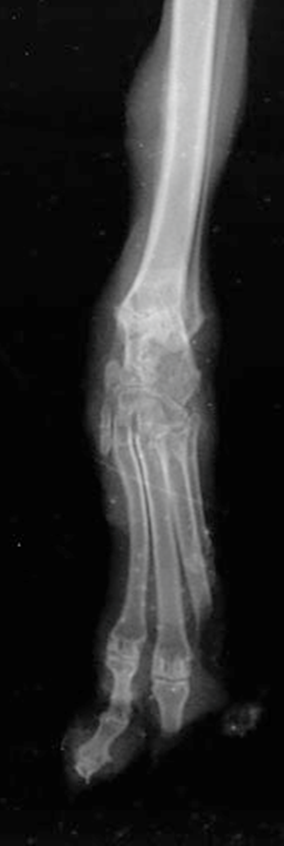

視診に基づくグレーディングに加え、深部組織への波及を確認するための多角的な検査が必要となります。感染が疑われる場合は、病変部からの培養および感受性試験を行います。Grade IV および V の疑いがある場合、X線検査は必須となります。骨の融解、骨膜の反応、関節腔の狭小化や消失を確認します 。中足骨や趾骨の微細な変化を捉えるために、X線よりも感度が高いCT検査が推奨されます。